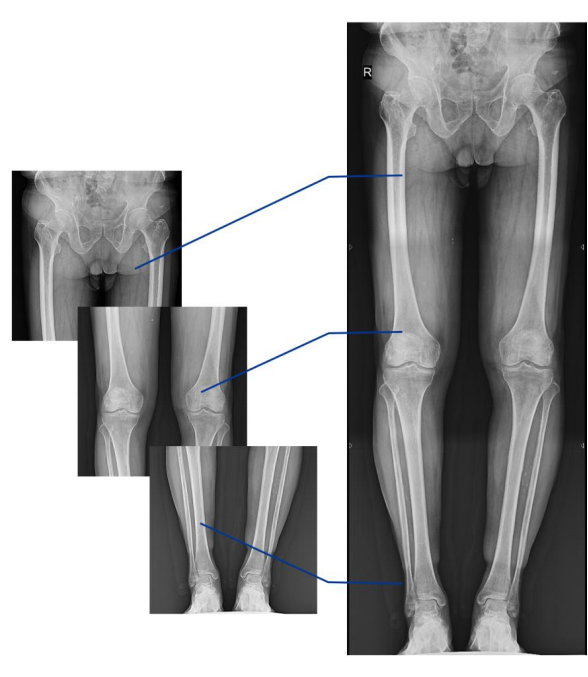

不同于常規(guī)靜態(tài)DR只能進(jìn)行平片攝影檢查,動(dòng)態(tài)DR可以滿足多種臨床檢查需求,包括靜態(tài)檢查、透視檢查、造影檢查、脊柱及下肢全長拼接檢查,相較于靜態(tài)DR具有豐富的臨床應(yīng)用,且動(dòng)態(tài)DR檢查更精準(zhǔn)、直觀,擺位攝片效率極大地提升,大大節(jié)省拍片時(shí)間。

更多高級(jí)智能應(yīng)用

動(dòng)態(tài)DR影像采集幅面大,17×17英寸超大視野,可覆蓋成年人的全胸全腹,并且能在連續(xù)動(dòng)態(tài)中實(shí)時(shí)高清點(diǎn)片,還可以進(jìn)行視頻保存,在會(huì)診過程中可以回放影像檢查視頻,從而達(dá)到精準(zhǔn)診斷的目的。同時(shí)動(dòng)態(tài)DR還具有全身拼接功能,尤其適用于全脊柱和全下肢攝影,輔助脊柱畸形矯形治療、康復(fù)檢查,為臨床提供高精度圖像。